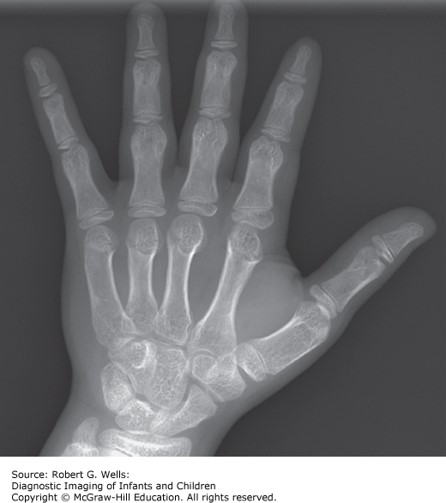

On physical examination, growth parameters show height 60 cm (<5th percentile), head circumference 46 cm (>95th percentile). You note macrocephaly, frontal bossing, flat nasal bridge, hypoplasia of the maxilla, rhizomelic shortening of the extremities, lumbar lordosis, and short hands and feet.

Achondroplasia is characterized by abnormal bone growth that results in short stature with disproportionately short arms and legs, a large head, and characteristic facial features. The clinical features include short stature, rhizomelic (proximal) shortening of the arms and legs with redundant skin folds on limbs, limitation of elbow extension, trident configuration of the hands, genu varum (bow legs), thoracolumbar gibbus in infancy, exaggerated lumbar lordosis, which develops when walking begins, large head with frontal bossing, and midface hypoplasia. Turner syndrome is characterized by short stature but not by macrocephaly or the other clinical features noted. Hypochondroplasia is very similar to achondroplasia but is typically less severe and does not have the facial features listed. OI is a disease characterized by bone fractures.

Photo: Wells RG. Diagnostic Imaging of Infants and Children; 2015.